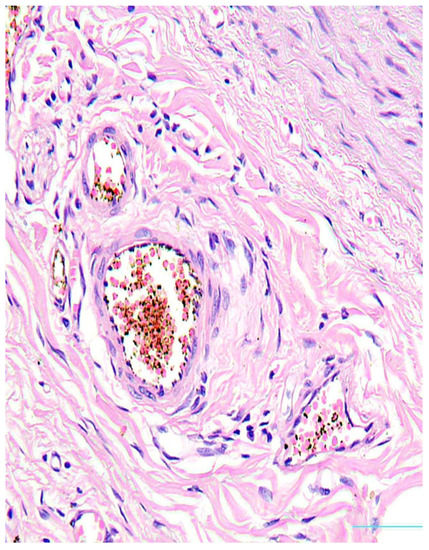

Histological Changes in the Popliteal Artery Wall in Patients with Critical Limb Ischemia

by Octavian Andercou, Maria Cristina Andrei, Dan Gheban, Dorin Marian, Horațiu F. Coman, Valentin Aron Oprea, Florin Vasile Mihaileanu, Razvan Ciocan, Beatrix Cucuruz and Bogdan Stancu

Diagnostics 2024, 14(10), 989; https://doi.org/10.3390/diagnostics14100989 - 8 May 2024

Introduction: This prospective study aims to illustrate the histopathological arterial changes in the popliteal artery in peripheral arterial disease of the lower limbs. Material and method: A total of 60 popliteal artery segments taken from patients who had undergone lower limb amputation were [...] Read more.

Introduction: This prospective study aims to illustrate the histopathological arterial changes in the popliteal artery in peripheral arterial disease of the lower limbs. Material and method: A total of 60 popliteal artery segments taken from patients who had undergone lower limb amputation were examined between April and June 2023. The degree of arterial stenosis, medial calcinosis, and the vasa vasorum changes in the arterial adventitia were quantified. The presence of risk factors for atherosclerosis was also observed. Results: Atherosclerotic plaque was found in all of the examined segments. Medial calcinosis was observed in 40 (66.6%) of the arterial segments. A positive association between the degree of arterial stenosis and the vasa vasorum changes in the arterial adventitia was also found (p = 0.025). The level of blood sugar and cholesterol were predictive factors for the severity of atherosclerosis. Conclusions: Atherosclerosis and medial calcinosis are significant in patients who underwent lower limb amputation. Medial calcinosis causes damage to the arterial wall and leads to a reduction in responsiveness to dilator stimuli. Full article